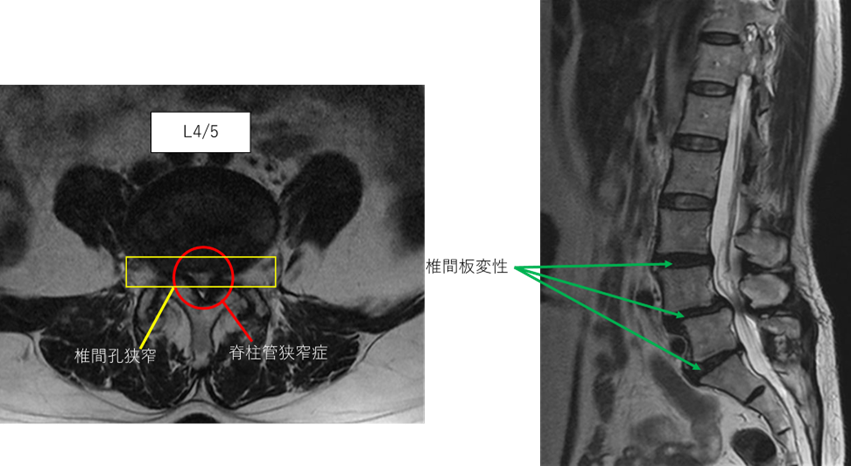

画像及び所見について

L1/2: 異常なし

L2/3: 異常なし

L3/4: 椎間板変性症

L4/5: 椎間板変性症、脊柱管狭窄症、椎間孔狭窄

L5/S: 椎間板変性症、繊維輪断裂

以上の事が画像上認められます。

L3/4、4/5、5/s に

椎間板変性症、脊柱管狭窄症、椎間孔狭窄、繊維輪断裂を認め、主症状の原因の可能性が高い。